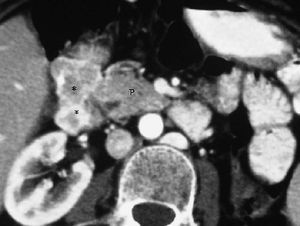

El duodeno también puede verse afectado tanto por extensión de tumores vecinos, siendo los más frecuentes los de estómago, como por neoplasias de colon transverso, páncreas (fig. 21), vesícula, hígado y riñón derecho1,2 (fig. 22).

Fig. 21--Neoplasia de páncreas. (A) Corte transversal de ecografía en el que se aprecia masa pancreática (P) que infiltra la pared duodenal (D). (B) Tomografía computarizada con contraste intravenoso correspondiente, donde se puede observar dilatación gástrica por la obstrucción.